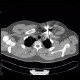

Both CT sections and radiographs show a foreign body of metallic density with metallic artifacts on CT which is lodged in the chest wall anteriorly to the sternal end of the left collar bone.